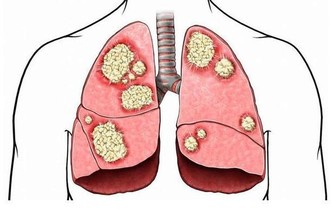

2、 水毒和瘀血堆積

這五種毒素是女性衰老催化劑,必須盡快排出

水毒是人體體液分佈不均勻時發生的,也就是體內發生水代謝異常的狀態。瘀血是人體內老、舊、殘、污血液,是氣、血、水不通暢的病態表現和毛細血管末梢循環不利的產物。水毒會引起病理的滲出及異常分泌等,也會出現發汗排尿的異常和水腫。瘀血的產生會引起對細胞、肌肉的養分、氧氣供應不足,引發腰酸背痛,同時身體表面溫度降低,有寒冷感。這些都會導致女性提早衰老。